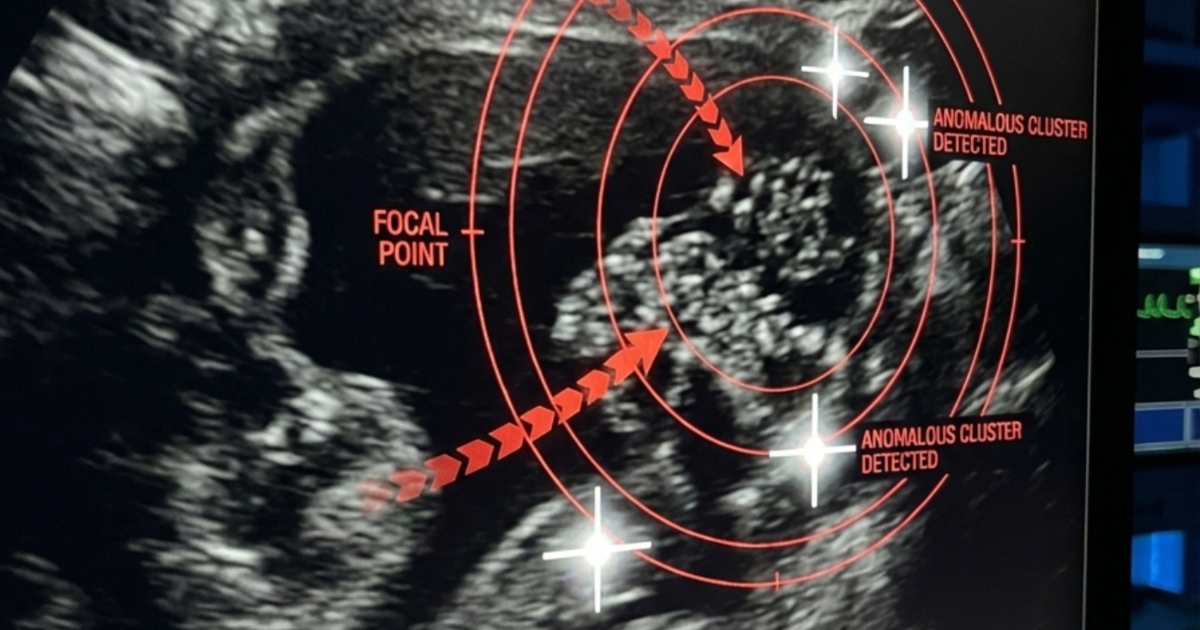

Chodby pohotovosti se zdály zmrzlé v čase. Sledujíc dceru, jak se kroutí na nosítkách v bolesti, čekaly jsme na výsledky ultrazvuku pod obavnými pohledy lékařů. Nakonec k nám přišel doktor a pronesl větu, kterou žádný rodič nechce slyšet: „Je nutná okamžitá operace.“ Ukázalo se, že ty bolesti zad, které jsme připisovali batohu, byly ve skutečnosti způsobeny tiše rostoucím ledvinovým kamenem. Kámen se posunul do močovodu, což způsobilo nesnesitelné bolesti a ohrožení života.